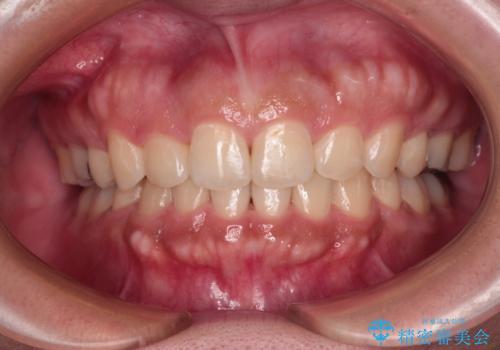

上顎歯列幅を拡大したことで、デコボコを容易に解消することができるようになったため、抜歯により得られたスペースを口元の突出感改善に利用することができました。